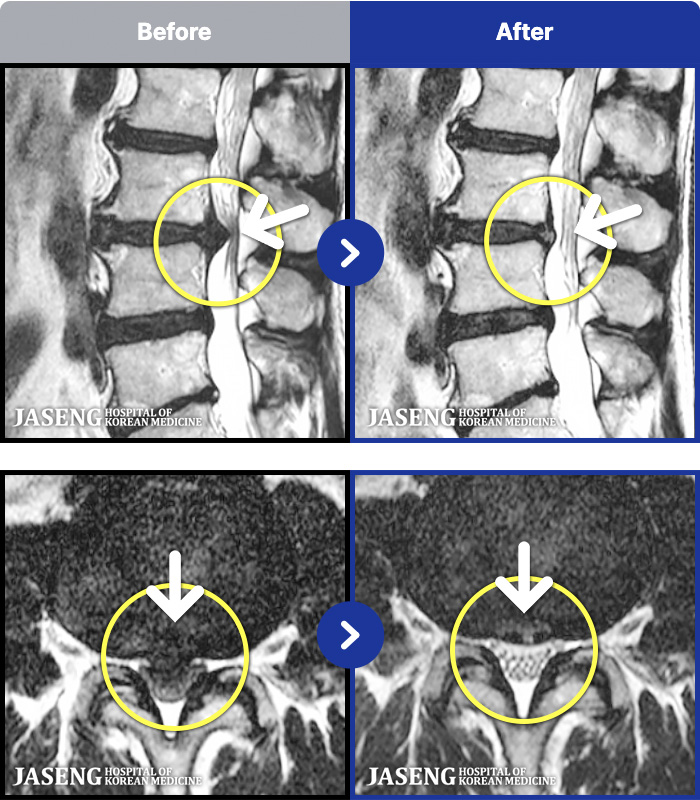

1,287 MRI ũ ʸ Ȯϼ.

[ϻ] 24.07.25~25.08.01